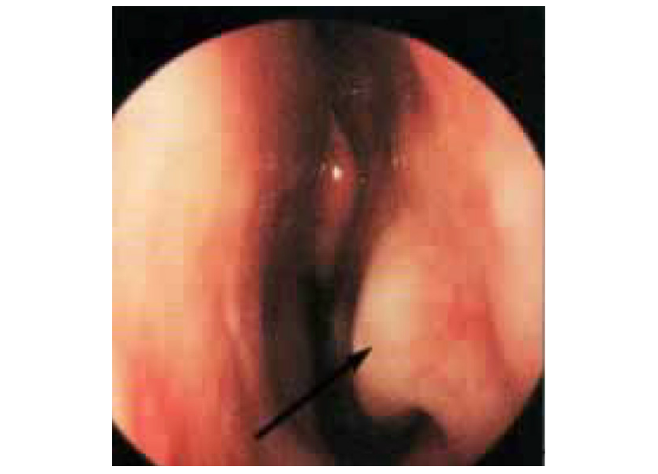

Turbinato normale

Lieve Ipertrofia

Marcata ipertrofia

Intervento in Radiofrequenze

Al termine del trattamento con radiofrequenza dell’ipertrofia dei turbinati, lo spazio respiratorio nasale risulta notevolmente aumentato.